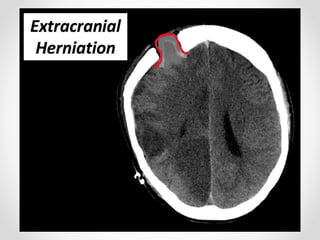

5. Thoát vị ngoài sọ

- Nhu mô não chui qua vùng khuyết sọ sau phẫu thuật

mở sọ giải áp hoặc sau chấn thương.

- Phù não thường xuất hiện trong tuần đầu sau PT giải

ép

- Nếu lỗ mở không đủ lớn, mô nãp phù sẽ lồi qua tạo

hình ảnh mũ nấm-> chèn ép TM vỏ não gây nhồi máu

tĩnh mạch và đụng dập mô não cạnh viền mở sọ